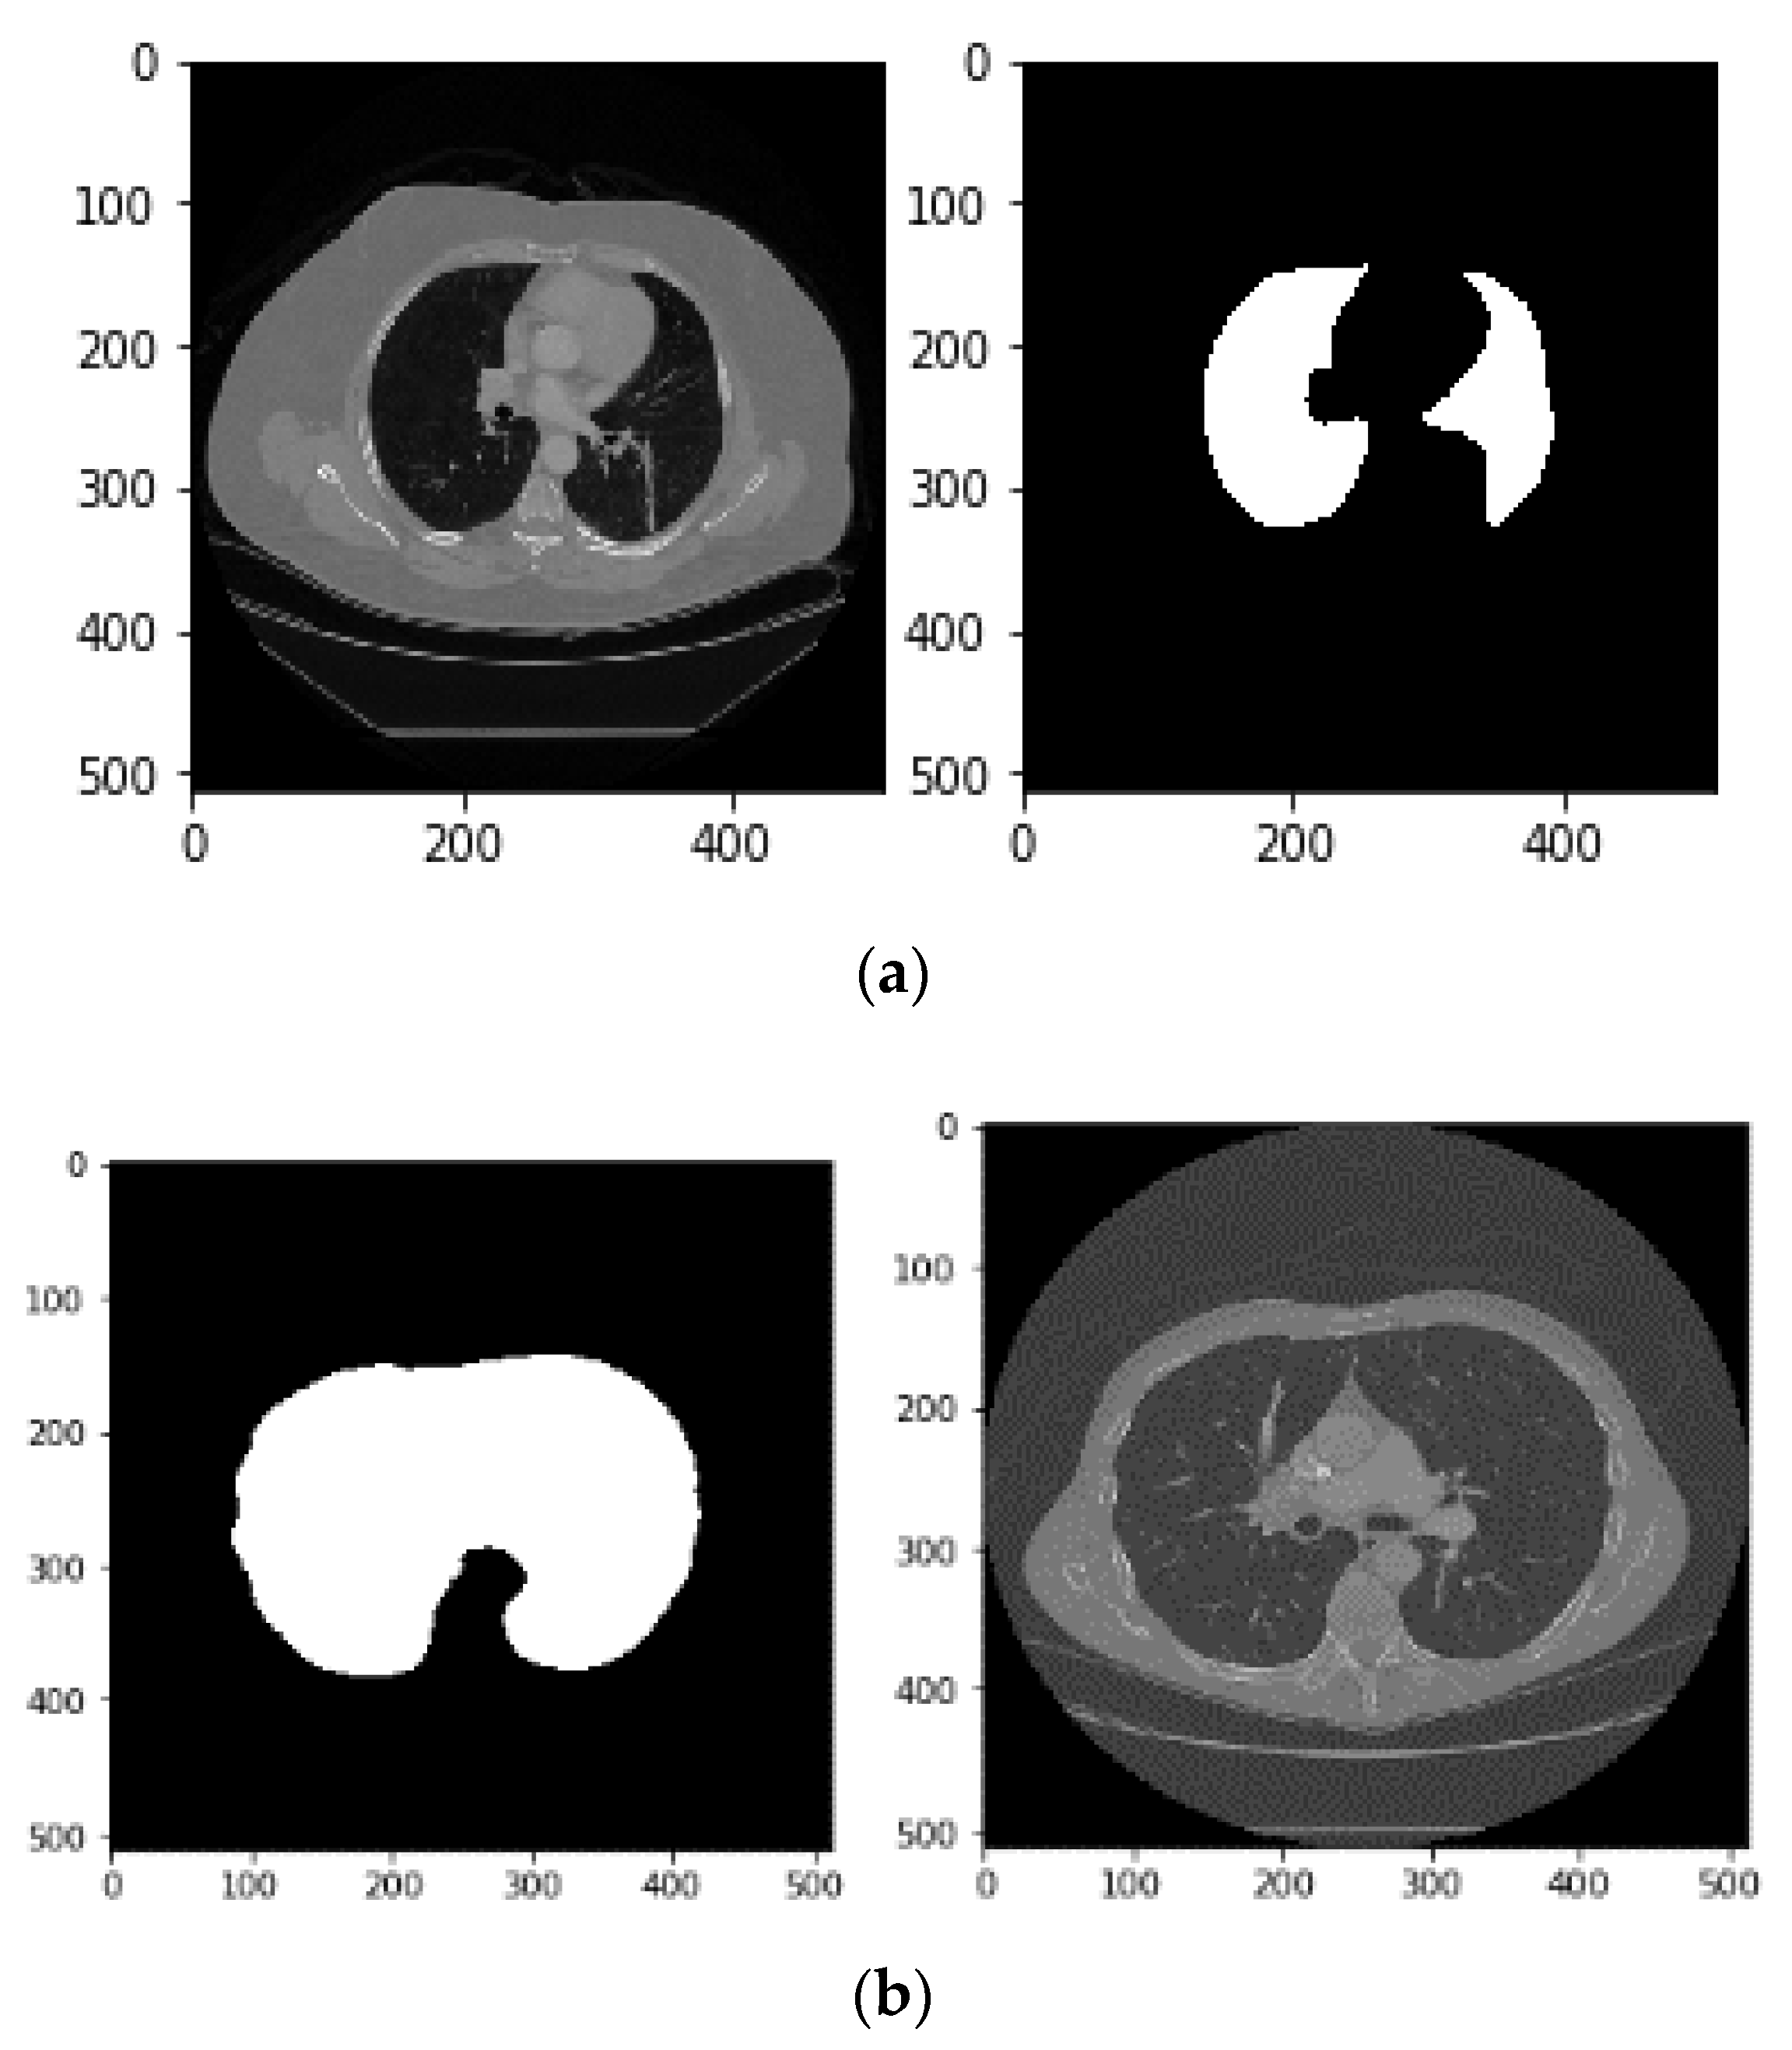

- Keeping the labels with two largest areas: As shown in Figure 5b, labels with the two largest areas (both lungs) are kept whereas the tissues with areas less than the expected lungs are removed.

- Applying erosion operation (with a disk of radius 2): This operation is applied on the image at this step to separate the pulmonary nodules attached to the lung wall from the blood vessels. The erosion operator reduces the bright areas of the image and makes the dark areas appear larger as shown in Figure 6a.

- Applying closure operation (with a disk of radius 10) [15]: The aim of using this operator is to maintain the nodules connected to the lung wall. This operator can remove small dark spots from the image and connect small bright gaps. The image obtained by applying this operator is shown in Figure 6b.

- Filling in the small holes within binary mask: In some cases, due to a breach in binary conversion using thresholding, a series of black pixels belong to the background appear in the binary image. These areas, known as holes, may be helpful. Therefore, we must obtain these areas by filling them as shown in Figure 6c.